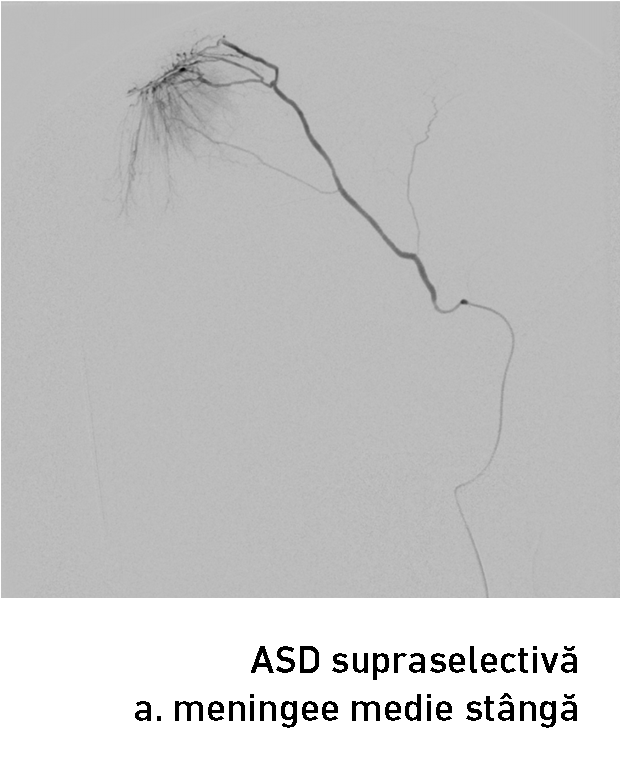

Tratamentul  endovascular al unei tumorii constă în introducerea agenților embolici înpediculii arteriali ce alimentează tumora până la ocluzia lor. Embolizarea tumorii poate fi realizată nemijlocit înaintea intervenției sau câteva zile în prealabil. Ocluzia arterelor ce alimentează tumora determină apariția leziunilor ischemice intratumorale (necroză centro-tumorală) și la nivelul atașamentului dural al meningiomului. În cazul dat am optat pentru embolizarea AMM stângi cu particule emboligene de 150-250 mcm care avansează intratumoral și în final realizează ocluzia mecanică al arterei feeder. A fost realizat cateterismul supraselectiv al AMM cu un microcateter (fig. 5-6) și prin el s-au injectat agenții embolici. Angiografia selectivă a arterei carotide externe stângi a confirmat diminuarea semnificativă al blush-ului tumoral și ocluzia AMM stângi (fig. 7).

endovascular al unei tumorii constă în introducerea agenților embolici înpediculii arteriali ce alimentează tumora până la ocluzia lor. Embolizarea tumorii poate fi realizată nemijlocit înaintea intervenției sau câteva zile în prealabil. Ocluzia arterelor ce alimentează tumora determină apariția leziunilor ischemice intratumorale (necroză centro-tumorală) și la nivelul atașamentului dural al meningiomului. În cazul dat am optat pentru embolizarea AMM stângi cu particule emboligene de 150-250 mcm care avansează intratumoral și în final realizează ocluzia mecanică al arterei feeder. A fost realizat cateterismul supraselectiv al AMM cu un microcateter (fig. 5-6) și prin el s-au injectat agenții embolici. Angiografia selectivă a arterei carotide externe stângi a confirmat diminuarea semnificativă al blush-ului tumoral și ocluzia AMM stângi (fig. 7).